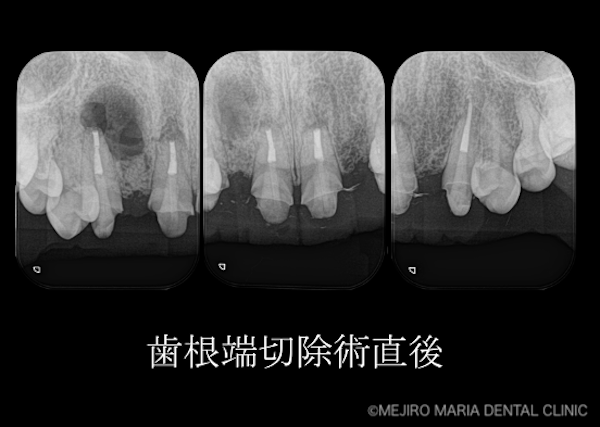

精密根管治療(歯内療法)終了後、患者様は術前同様に、特に症状は訴えていませんでした。しかし治療終了から3ヶ月経っても、病変の縮小は確認できませんでした。

患者様は今後、セラミックによる被せものを製作して、今回治療した歯に装着する予定があります。そのため、根尖性歯周炎の悪化を予防する意味も含めて歯根端切除術を行い、病変を完全に治癒させることをご提案いたしました。

今回の症例は、現状では日常生活に影響を与えるような症状は出ていない根尖性歯周炎でした。しかしその病変は大きく、通法の根管治療では治癒に至らなかったため、歯根端切除術を行いました。